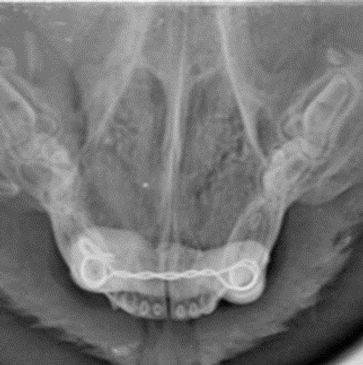

Extractions can often be complicated by severe periodontal disease, cyst formation, or unerupted teeth. Surgical ex tractions can be performed for complicated cases. Goals are to minimize bone loss. Bone graft placement can enhance new bone formation with the goal of maintaining bone height around the adjacent teeth.